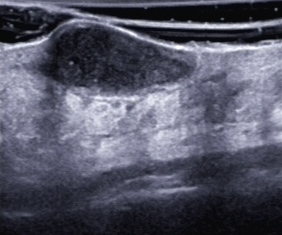

Eine erneute lokale sowie antibiotische Therapie führten zunächst zu einem Teilerfolg, jedoch wurde die Patientin bereits nach wenigen Wochen erneut vorstellig – es war wieder zu einer Abszedierung gekommen (sonografische Darstellung, s. Abb. 4–6)